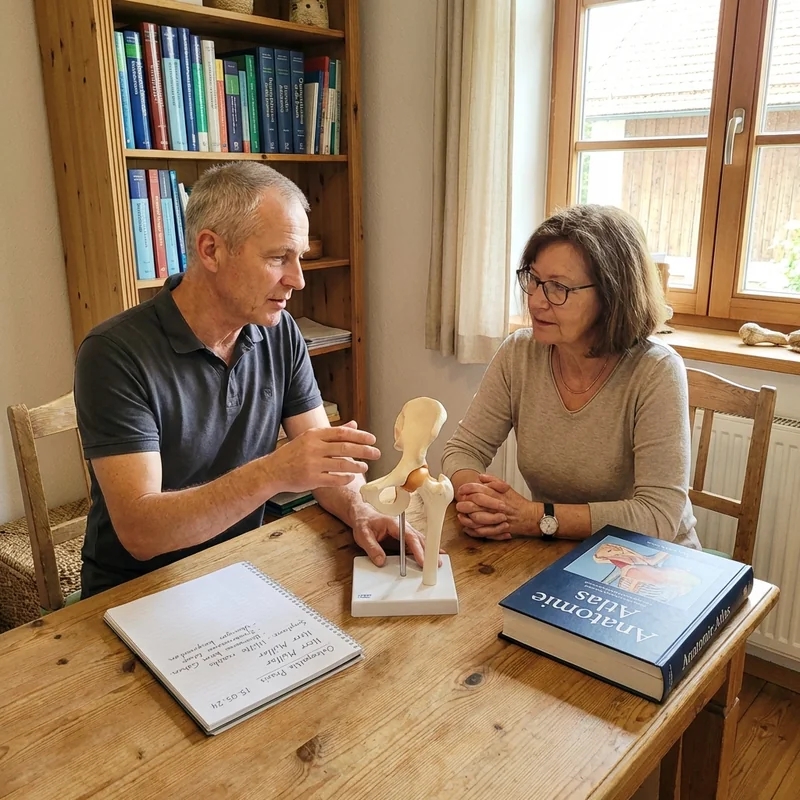

Der Termin, der alles veränderte

Jürgen Brandt. 58, seit über zwanzig Jahren Gelenkpatienten. Kein Wunderheiler — ein Therapeut, der sich Zeit nimmt.

Er hörte sich Monikas Geschichte an.

Dann stellte er eine Frage.

„Frau Wegner, wie lange nehmen Sie schon Ibuprofen?"

„Seit zwei Jahren. Jeden Abend."

„Dann muss ich Ihnen etwas sagen, das Ihnen Ihr Orthopäde wahrscheinlich nicht gesagt hat."

Was Brandt ihr dann erklärte, war einfach — und erschütternd.